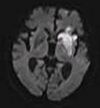

| Fluid-attenuated inversion recovery |

FLAIR |

Fluid suppression by setting an inversion time that nulls fluids |

High signal in lacunar infarction, multiple sclerosis (MS) plaques, subarachnoid haemorrhage and meningitis (pictured).[74] |